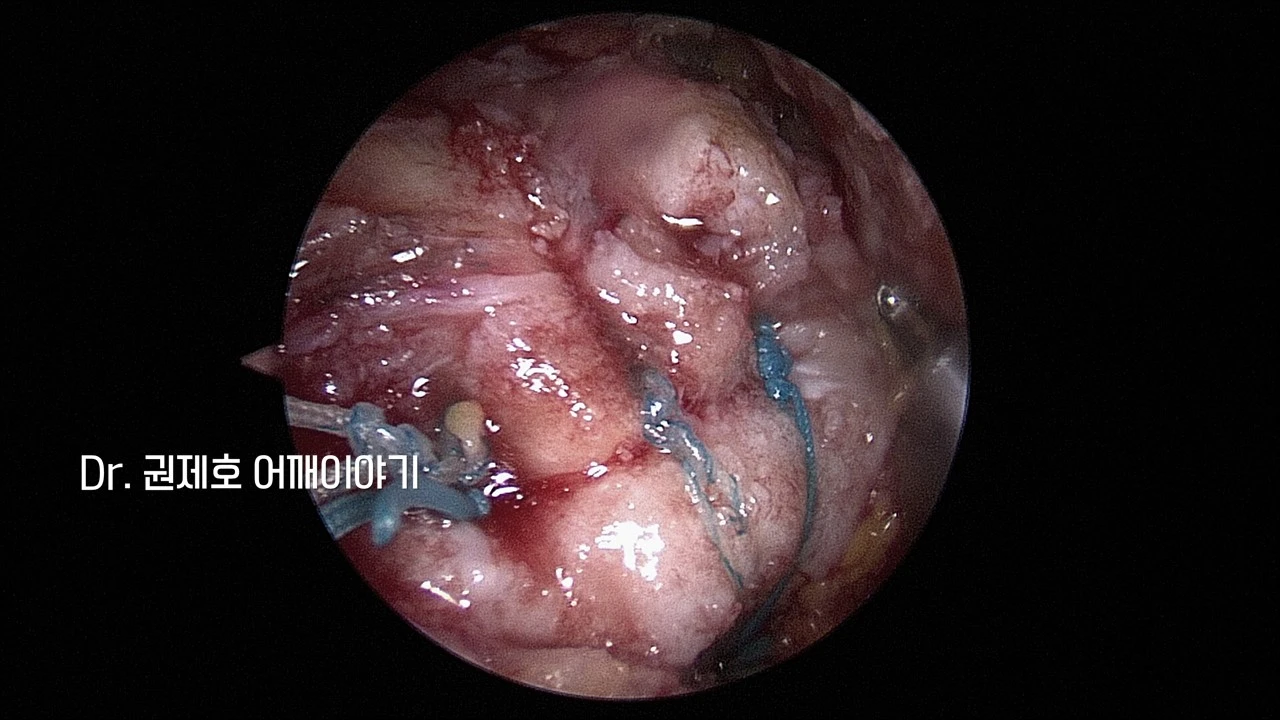

어떤 모양으로 찢어졌고, 헤졌는지를 파악한 후 어느 방향으로 봉합 수술할지 결정이 되고 나면, 이제 봉합사를 삽입하여 본격적으로 봉합수술을 진행한다. 위 사진에서는 봉합사를 뼈에 심고 나서 실들이 나온 모습들이다.

이렇게 인대 끊어짐이 있은 후 헤지고, 말려버리면, 단순 봉합은 힘들다. 따라서 시간이 조금 더 걸릴지언정, 이중으로 봉합 수술하는 것이 더 좋은 결과를 기대할 수 있다. 이중 봉합을 어깨관절경 회전근개 브리지 봉합수술이라고 한다.